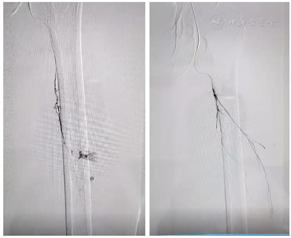

甲泼尼龙500mg×3天,继以逐渐减量(250mg×3天、160mg×3天、80mg×5天);环孢素75mg,bid;环磷酰胺0.8g qw×3次,余予以全覆盖抗感染以及吡非尼酮600mg tid /d抗纤维化治疗。患者于11月21日诉左侧大腿肿痛。血常规:血红蛋白:65g/L;血小板:89×109/L。凝血功能PT14.4秒、APTT42.1秒、纤维蛋白原1.24g/L。不能排除下肢肌间出血可能,急行床边B超:左大腿软组织区包块--血肿?行下肢动脉CT:考虑左侧大腿肌间血肿形成(图5)。介入科会诊后行超选择性左侧股深动脉-穿动脉栓塞术(图6)。患者出血停止,血肿吸收,好转出院。目前仍在随访中。